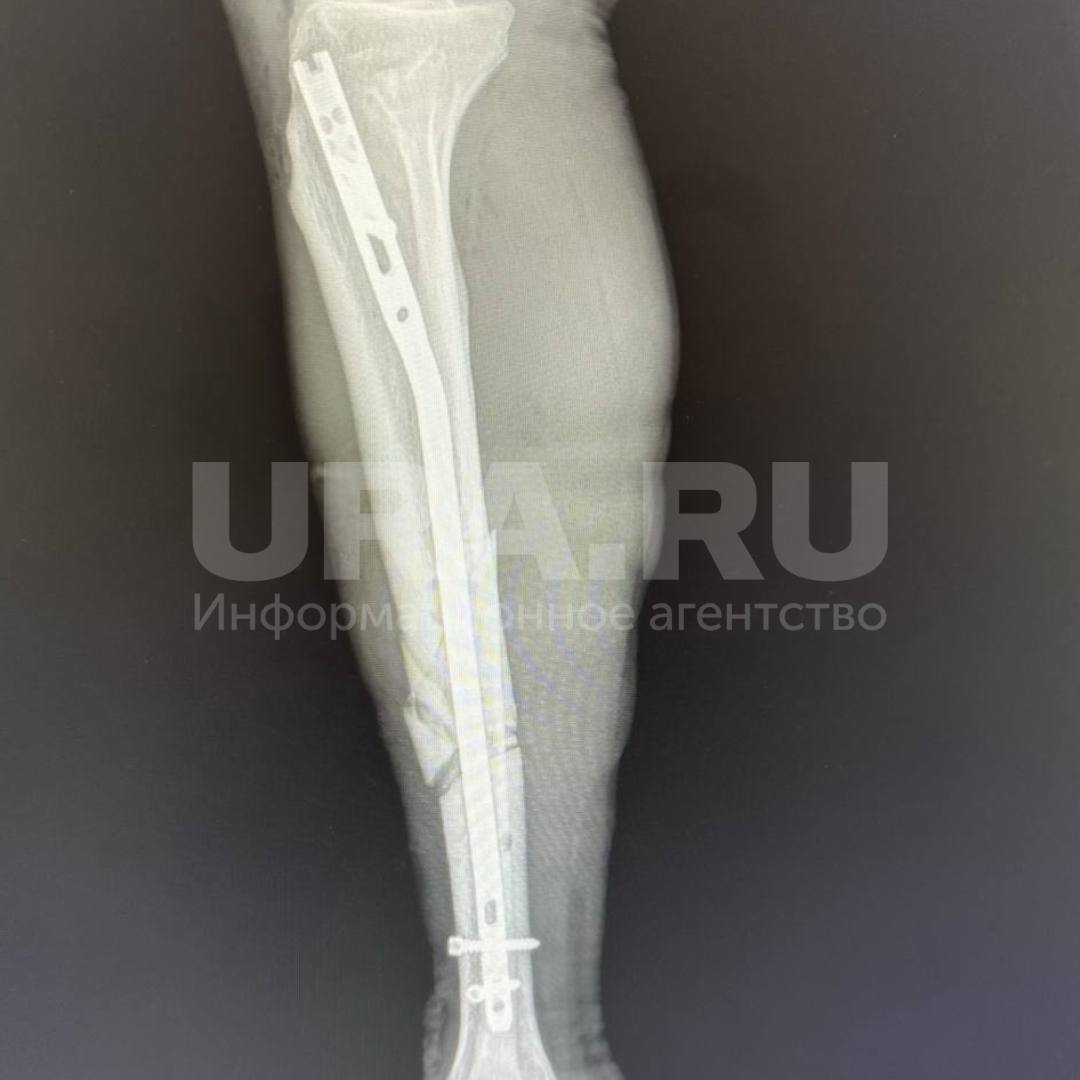

Упал с 32-го этажа и остался жив. Хирурги два месяца заново собирали скелет рабочего, сорвавшегося на стройке. По информации URA.RU, монтажника спасло защитное сооружение, на него он рухнул пролетев 20 этажей. Получил 10 переломов: носа, обоих плечей, ребер, костей таза и ног. Одно легкое оказалось разорванным. К жизни пациента вернули в НОКБ им. Семашко.